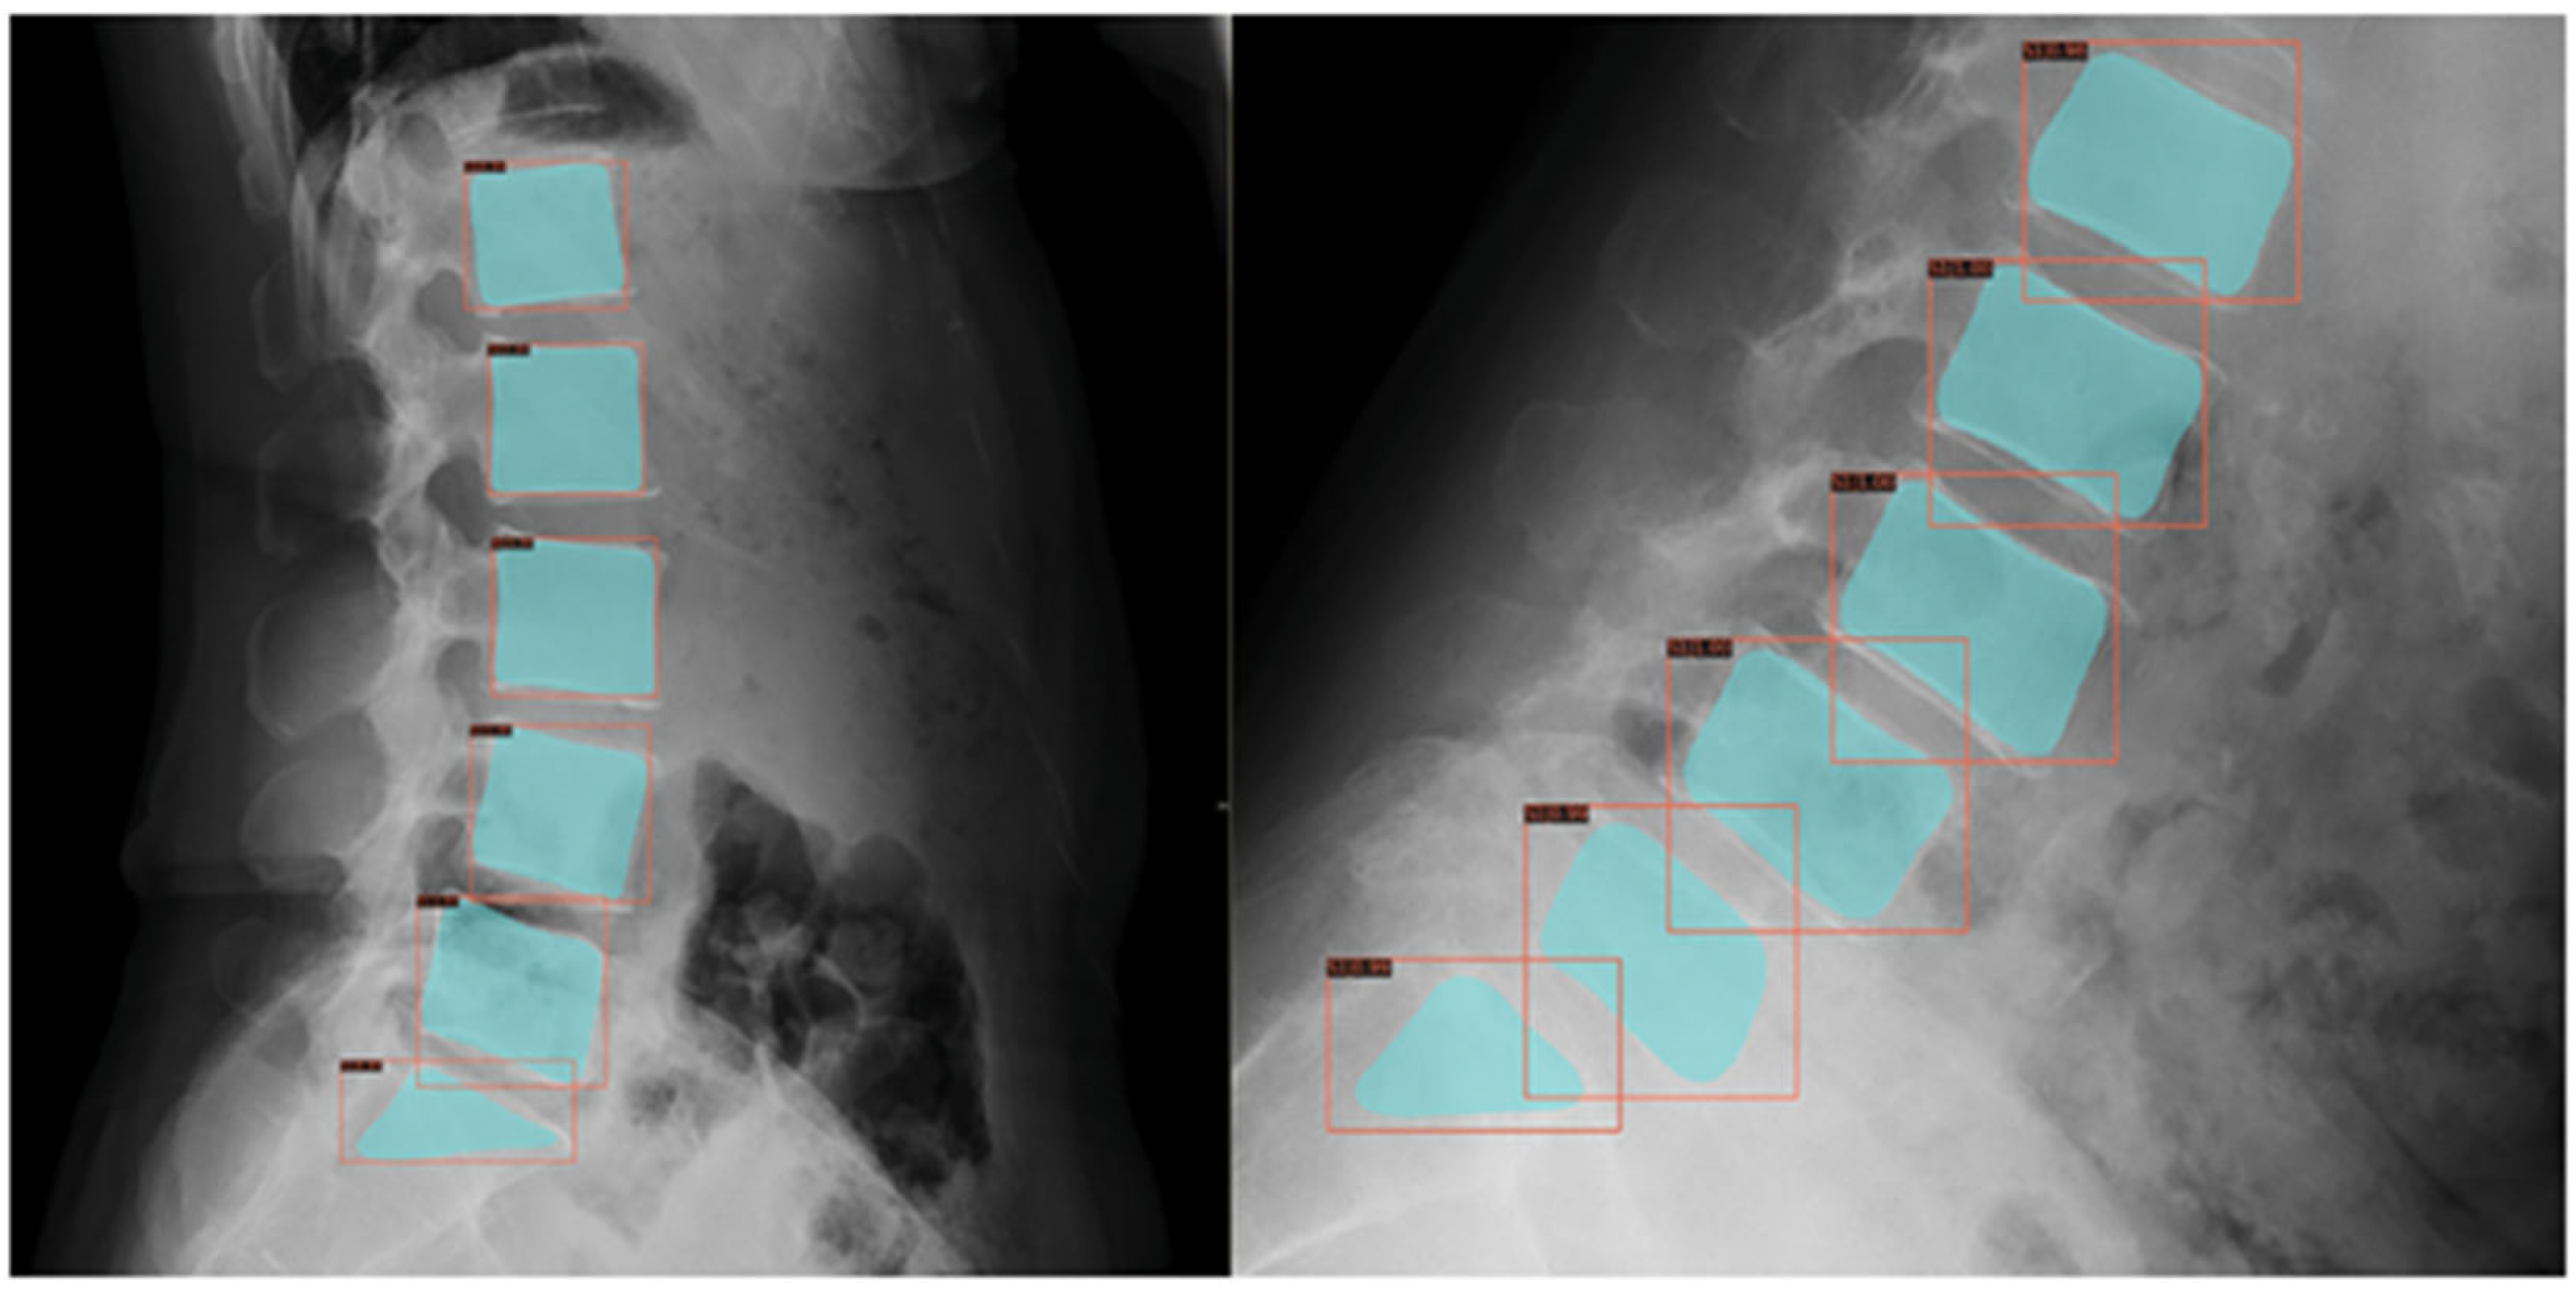

As unsupervised learning identifies patterns without labels, it is useful for patient clustering. A single-center study applied semi-supervised clustering to 111 adolescent sagittal spine radiographs, identifying three to five distinct alignment groups, with sagittal vertical axis found as a key differentiator to classify scoliosis subtypes or treatment responses. This still lacked external validation and generalizability assessment [

Figure 4), although primarily studied in adults [

20].